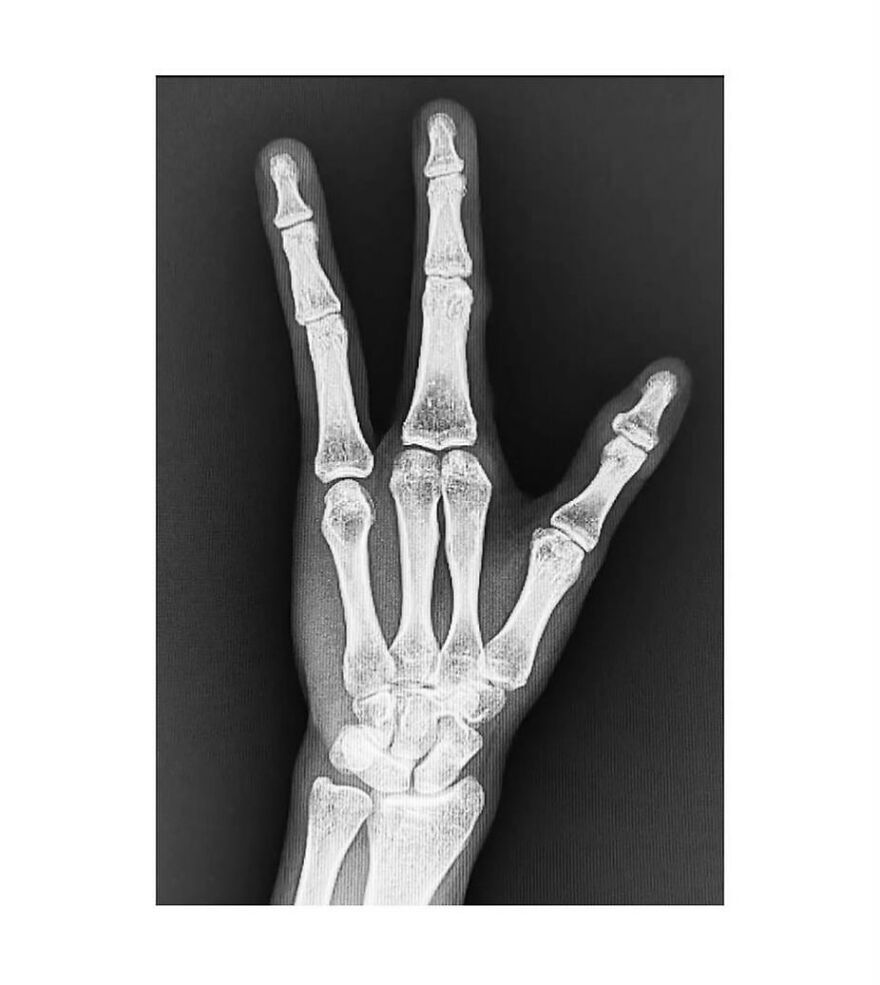

This is a birth defect, I think it's referred to as "crab hands."